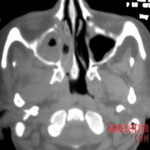

Further examinations, including blood tests, did not reveal diabetes or other common conditions that could explain the symptoms. However, it was evident that the body was fighting a severe infection. A crucial turning point came with a CT scan, which revealed extensive damage to the maxillary bone and spread of inflammation into the paranasal sinuses, including the deeper ones. Fortunately, the brain and eye sockets were not yet affected.